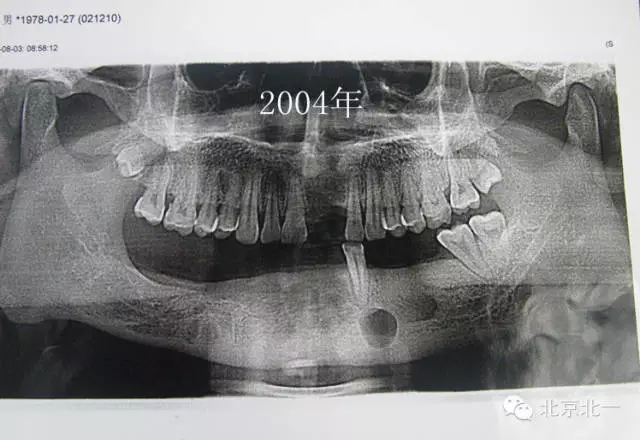

患者男,33歲,左下頜囊腫復發(fā)兩次就診。

圖一、初診時全景片